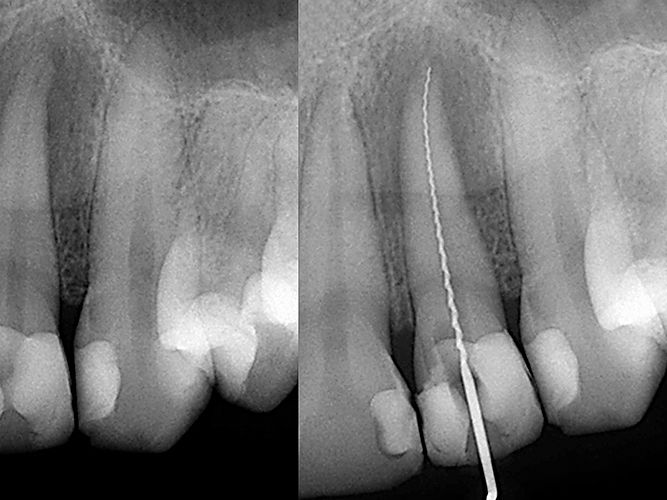

ROOT CANAL TREATMENT

Treatment includes removal of infected pulp and cleaning of root canal along with all digital radiography wherever needed. Treatment will be carried in a well sterilized environment with preferably endoradar and high ends endo instruments.